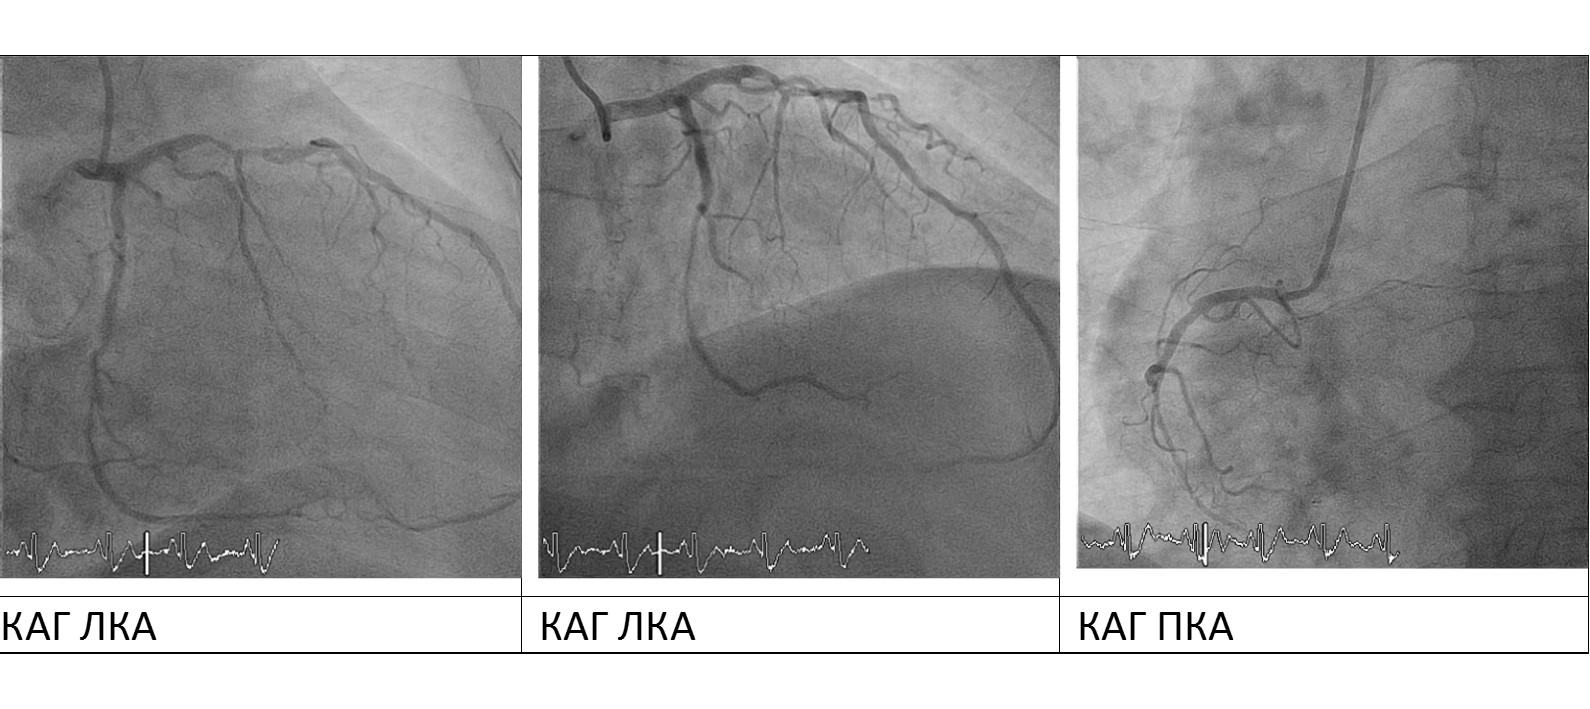

Пациенту в экстренном порядке радиальным доступом выполнена коронарография:

ЛКА – ствол: без значимых стенозов, ПМЖВ: неровность контуров, критический стеноз среднего сегмента до 90%, ОВ: неровность контуров, стенты в среднем и дистальном сегментах без признаков тромбоза и рестеноза. ПКА: неровность контуров, хроническая окклюзия дистального сегмента.